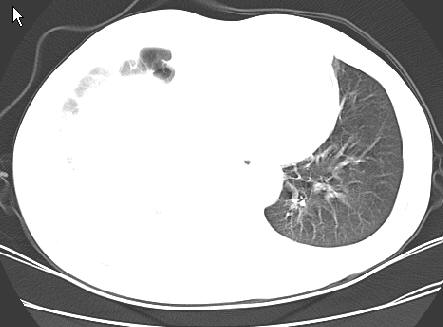

以下是引用草之原在2009-5-2 19:29:00的发言:[br]1.考虑右侧中心型肺ca纵膈淋巴结转移,双侧胸腔积液及右侧叶间裂积液,心包积液。[br]2.两肺上叶病灶,纵膈窗显示部分病灶硬化,考虑:结核。[br][br] [br]

以下是引用ct诊断高手在2009-5-2 19:08:00的发言:[br]我考虑右侧中央型肺癌 伴右肺节段性不张,两肺及纵隔淋巴结转移,右侧胸腔积液。

以下是引用zjzjr在2009-5-2 20:16:00的发言:[br]肺结核,转移瘤.纵隔淋巴结转移或淋巴瘤,右侧包裹性积液、斜裂积液。心包积液。